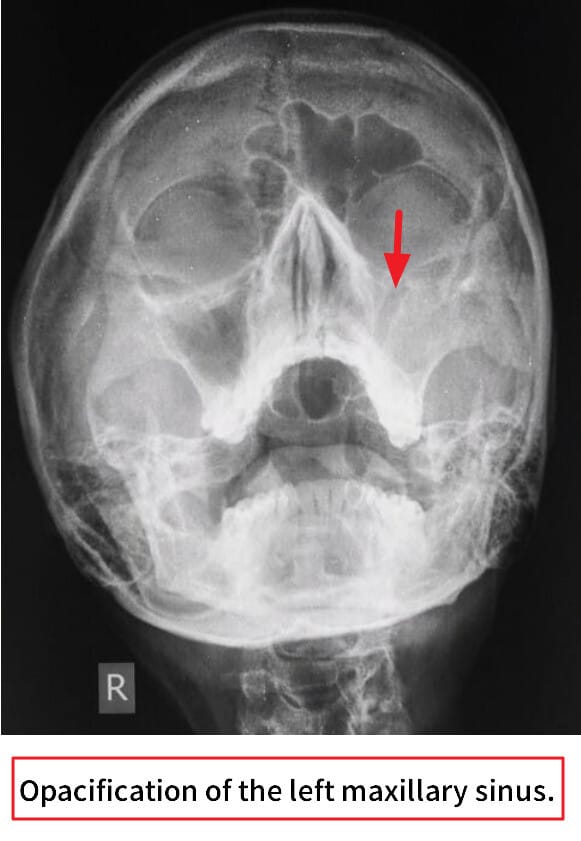

– 영상검사: Water’s view X-ray로 상악동의 air-fluid level 관찰.

– 비강 내시경: 농성 분비물, 점막 부종 확인